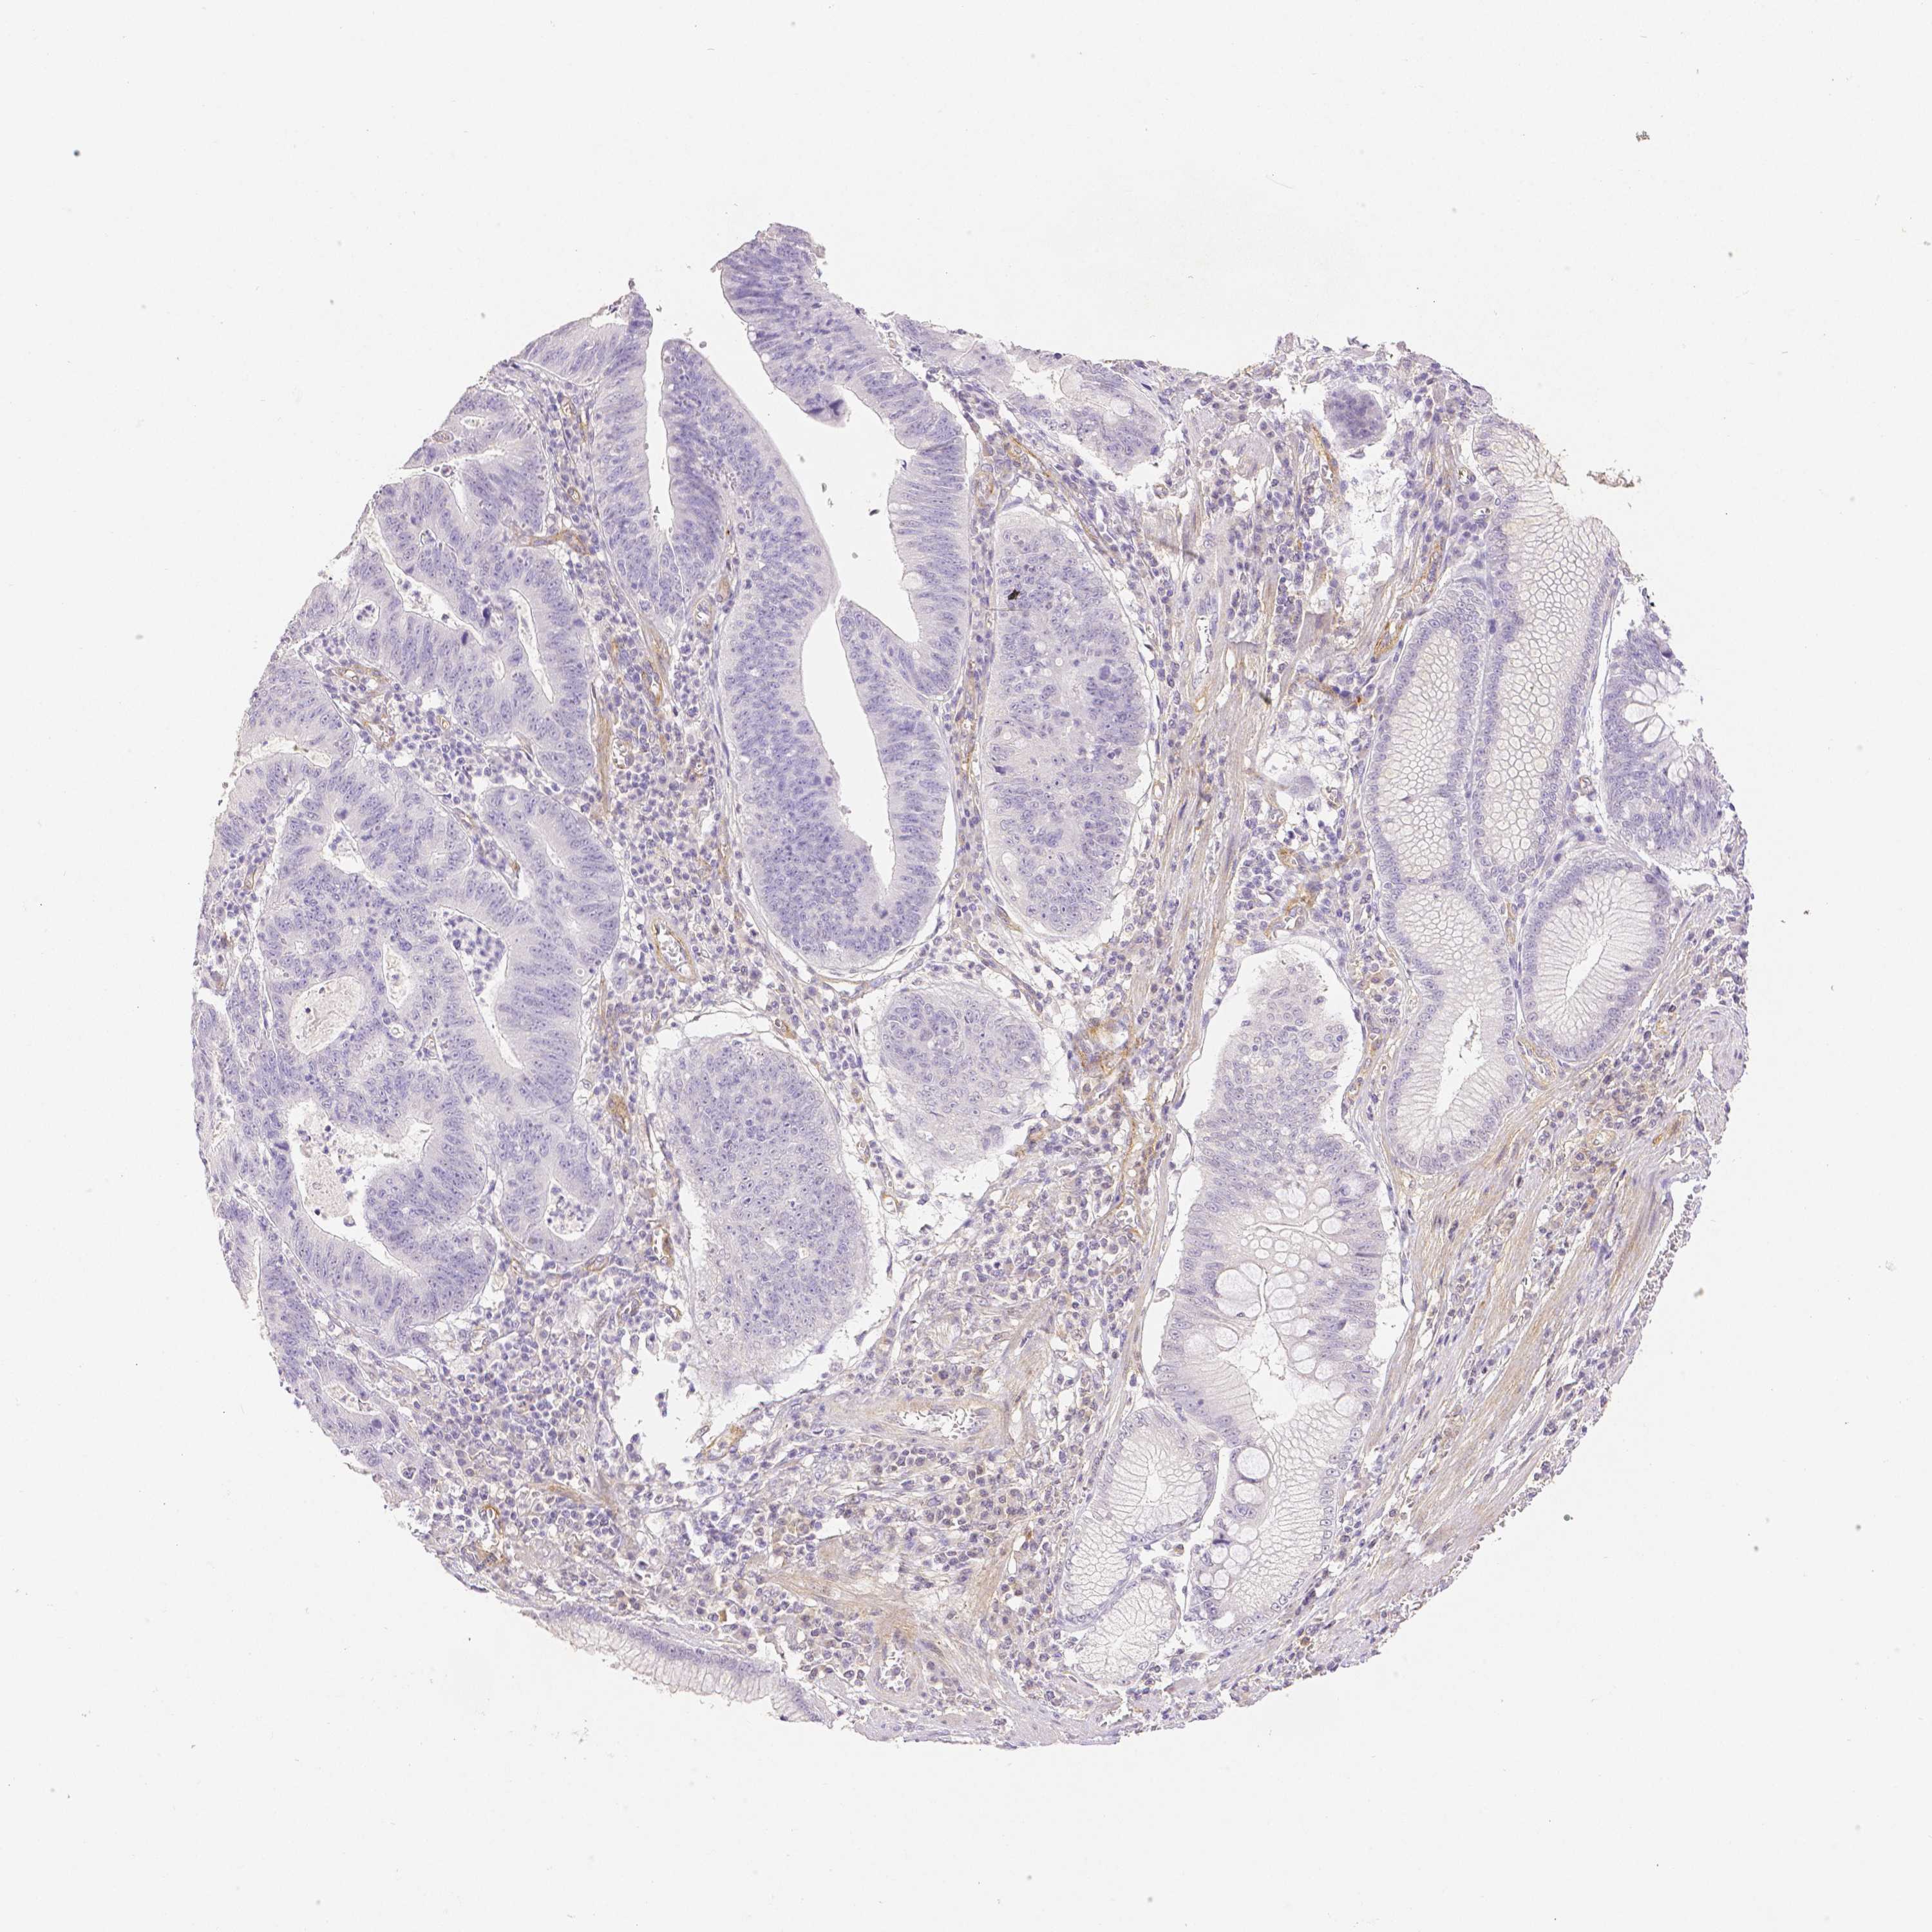

STOMACH CANCER - Protein expressioni

A mouse-over function shows sample information and annotation data. Click on an image to view it in a full screen mode. Samples can be filtered based on level of antibody staining by selecting one or several of the following categories: high, medium, low and not detected. The assay and annotation is described here.

Antibody stainingi

Antibody staining in the annotated cell types in the current human tissue is reported as not detected, low, medium, or high, based on conventional immunohistochemistry profiling in selected tissues. This score is based on the combination of the staining intensity and fraction of stained cells.

Each image is clickable and will lead to virtual microscopy that enables deeper exploration of all samples and also displays staining intensity scores, fraction scores and subcellular localization as well as patient and tissue information for each sample.

Antibody HPA003733

Antibody CAB068243

Antibody CAB068244

Staining

High

Medium

Low

Not detected

Intensity

Strong

Moderate

Weak

Negative

Quantity

>75%

75%-25%

<25%

None

Location

Nuclear

Cytoplasmic/membranous

Cytoplasmic/membranous,nuclear

Adenocarcinoma, NOS